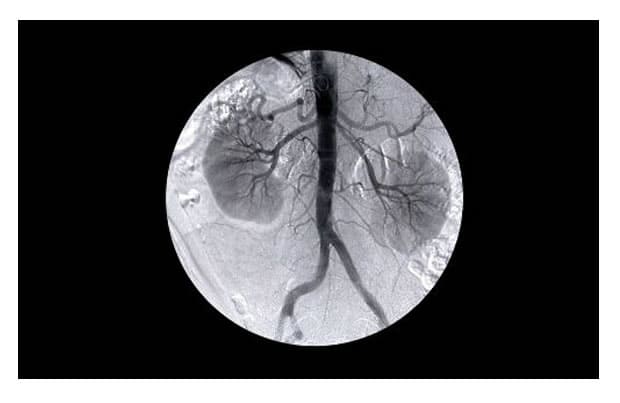

次は、腎臓に起こる合併症をみてみましょう。高血圧は腎臓にも大きな影響や 合併症を引き起こすことがあります。腎臓の内にあり、とても大切な働きをする糸球体 がありますが、これは細動脈の束です。高血圧は動脈に損傷を与えます。そして、糸球体高血圧に なるとレニン-アンギオテンシン系を賦活しようとし、さらに高血圧になり、腎臓に合併症を引き起こ すことがあるのです。

レニン‐アンギオテンシン系は血圧や細胞外容量のコントロールに関わるホルモン系の総称で、 腎臓内の糸球体は廃絶すると再生不能情たになります。つまり、糸球体障害が起きると残っている糸球体に さらに負荷をかけてしまうのです。その状態が続くと腎不全になり人工透析が必要になります。このように高血圧の合併症は腎不全すら悪影響を起こしかねません。